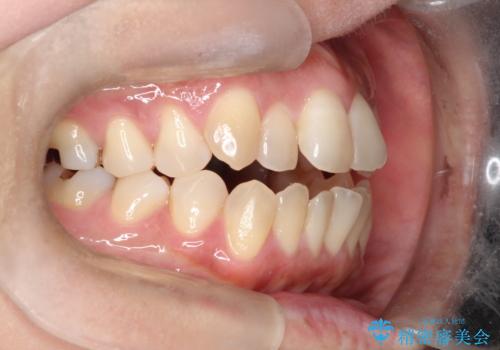

【開咬】笑った時の見た目を改善したい。

- 重度の開咬でしたがインビザラインで適切に治療計画を立て、きれいに仕上がりました。